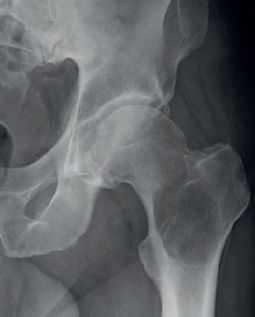

Обычно единичный очаг из плазматических клеток в костях обозначают как плазмоцитома, в то время как множественное поражение называют миеломной болезнью. Плазмоцитома практически не встречается у пациентов до 40 лет. Локализуется очаг чаще в осевом скелете. Множественные очаги при миеломной болезни также поражают кости таза, череп. Плазмоцитома возникает из костного мозга в виде безудержного размножения плазматических клеток (обычно IgG). Характерный белое Бенс-Джонса легко определяется в моче.

На рентгенограмма, КТ или МРТ поражение типично литическое, каплевидное, четко очерченное. При МРТ позвоночника такие очаги особенно отчетливо видны по замещению желтого костного мозга.

Рентгенограмма. Литический очаг в бедренной кости.